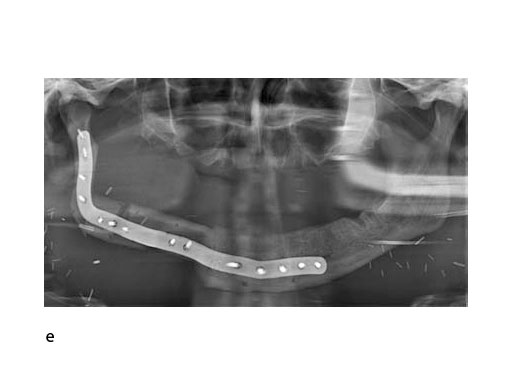

A 58-year-old male patient had oral cancer (T4n0m0) infiltrating the alveolar process and the anterior border of the ascending ramus (Fig 2). The treatment plan involved resection, bilateral neck dissection (levels I to III), and primary mandibular reconstruction with a right osteomyofasciocutaneous fibula flap.

At this stage, future dental implant insertion requires an alveolar process in a lingual shift position. To this end, the anterior segment is aligned with a medial offset. The posterior segment, which replaces the angle/anterior ramus region, is arranged with an overlapping zone. The inner cortex of the posterior segment in the area of intersection is trimmed to keep the restoration within the bounds of the original width of the angle. This results in a sort of "bayonet connection". The basal border of the mandibular body is not built up, since it is not functionally relevant.

With the design of the bony framework being ready, the reconstruction plate is molded to the geometry of the outer surface of the neomandibular division. The plate profile (thickness 2.0 or 2.5 mm) is chosen and the plate screw hole pattern is customized. Relative to the osteotomy sites, the fibular segment configuration, and the adjacent native bone, the number, position, and angulation (up to 15) of the plate screw holes is specified with respect to overall stability. A defined screw hole position facilitates accessibility for screw insertion and avoids interference with nerves, tooth roots, osteotomy interfaces, and existing/future implants.

To allow the soft tissue/vascular pedicled segments to shift into the "bayonet" assembly, a bone portion in between the segments has to be discarded. The inner cortex of the posterior segment needs appropriate trimming. The most distal cut along the fibula is placed about 5-6 cm above the ankle joint to preserve its stability.